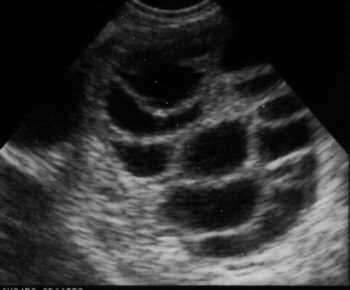

* Pelvic ultrasound scans are used to access the endometrium (lining of the womb), and to determine how the follicles are developing. Pelvic ultrasound is usually carried through the vagina to gain better resolution for the accurate assessment, to adjust the dose of medications, and to reduce the risk of developing hyperstimulation Blood tests may also be carried out to measure hormone levels and helps to determine when ovulation is imminent.